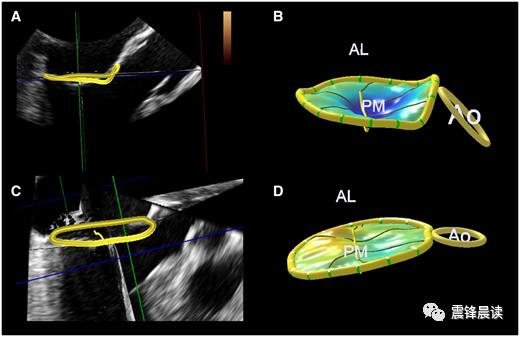

二尖瓣环的解剖,运动和临床意义(三)

二尖瓣

二尖瓣的解剖

二尖瓣解剖图